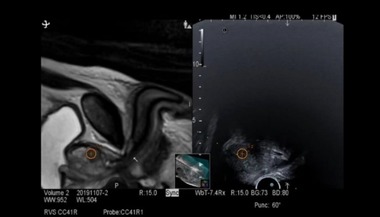

Unitatea medicală transmite că biopsia RMN-fusion combină imagistica prin rezonanţă magnetică multiparametrică (IRM/mp) cu ghidarea ecografică transrectală, permiţând medicului să identifice şi să preleveze ţesut exact din zonele suspecte identificate ale prostatei. Astfel, precizia diagnosticului creşte semnificativ.

Principiul procedurii se bazează pe suprapunerea imaginilor obţinute anterior prin RMN peste imaginile ecografice în timp real. Software-ul dedicat fuzionează cele două seturi de date, generând o hartă tridimensională detaliată a prostatei. Această abordare permite prelevarea ţintită a probelor din leziunile cu risc crescut, identificate anterior prin RMN ca fiind suspecte conform scorului PIRADS.

Procedura se realizează în cadrul Spitalului Satu Mare cu ecograful Fujifilm Arietta 880, cu anestezie generală intravenoasă, în regim de spitaşizare de zi, iar recuperarea este rapidă.